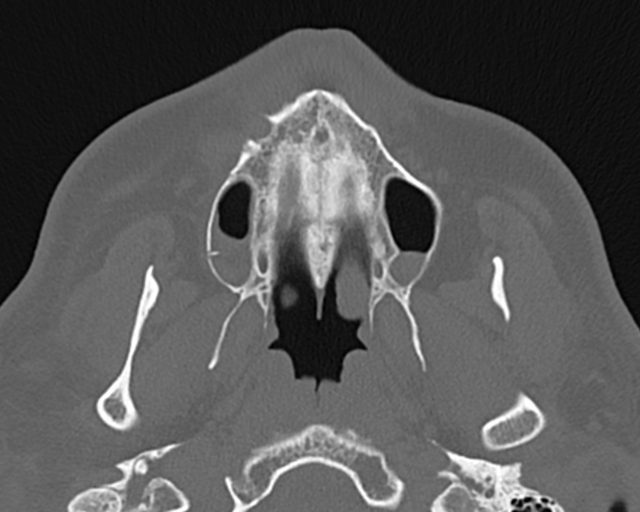

سی تی اسکن از سقف اربيت تا غضروف تيروئيد ( مقاطع تهيبدون کنتراست (مولتي ديدکتور 16 با مقاطع ظريف و بازسازي هاي ساژيتال و کرونال و 3D):

– انحراف سپتوم مياني بينی به چپ

– Fx با جابجايي خفيف در ديواره آنتريور سينوس ماگزيلاري راست با گسترش به ديواره فوقاني ( کف اربيت راست )

– FX با جابجايي در ديواره پوسترولترال اربيت راست همراه با هماتوم و دفورميتي سينوس

– Fx با جابجايي در ديواره لترال اربيت راست و گسترش به زايگوماي راست

– Fx سگمنتال با جابجايي در قوس زايگوماي راست

-retention cyst در کف سينوس ماگزيلاري چپ مشهود است .